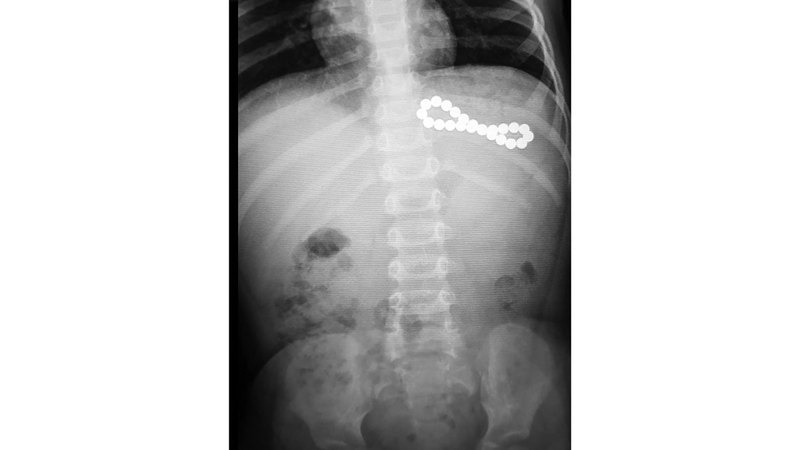

وأوضح أن نتائج الدراسة كشفت عن مؤشرات مقلقة، حيث تم تسجيل 114 حالة ابتلاع كرات مغناطيسية بين الأطفال خلال فترة البحث، لافتاً إلى أن من أخطر هذه الحالات طفلة تبلغ من العمر تسع سنوات في دبي ابتلعت 28 كرة مغناطيسية، إضافة إلى حالة أخرى لطفلة ابتلعت 26 كرة مغناطيسية.

وأشار إلى أن الدراسة وثّقت حالات استدعت تدخلات جراحية معقدة لإزالة سلاسل مغناطيسية أو علاج مضاعفاتها الخطيرة، مثل تكوّن نواسير بين المعدة والأمعاء، أو بين أجزاء الأمعاء نفسها، فضلاً عن تسجيل حالة نادرة لتكوّن ناسور بين المريء والقصبة الهوائية، ما استدعى استئصال الجزء المصاب جراحياً.

وبيّن أن التعامل الطبي مع هذه الحالات يعتمد على عدد الكرات ومكانها ووقت ابتلاعها، حيث يتم التقييم الفوري باستخدام الأشعة السينية لتحديد العدد والموقع. وفي حال ابتلاع كرة واحدة فقط، قد تتم المراقبة الدقيقة في ظروف محددة، أما عند ابتلاع أكثر من كرة، فلا يُنصح بالانتظار في معظم الحالات، فإذا كانت الكرات في المعدة، قد يتم استخراجها بالمنظار بشكل عاجل، أما إذا تجاوزت المعدة أو ظهرت علامات خطر، تصبح الجراحة الفورية ضرورة لا تحتمل التأجيل.